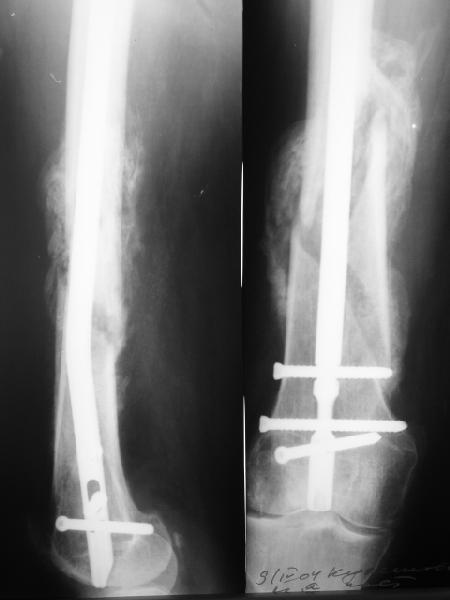

По прямой проекции неплохо. Что за стержень?

Антеградный остеосинтез при дистальных переломах бедра мы применяем давно, этот материал обобщен в канд. диссертации Александра Виноградского.

Примеры приложены.

Алекс, как Вы можете говорить, что "по прямой проекции неплохо"!? :( Гвоздь в суставе !!!

Снимаю свои претензии. На втором из снимков, которыми Вы хвастаетесь, гвоздь тоже в суставе, и ничего :(

И вообще мне кажется, что представленный ОС не допустим:1. стержень в суставе,2. неправильная длинна винтов, 3. ось конечности неправильная, 4. циркулярная гипсовая повязка после ОС?????

-1. стержень в суставе,

Это не критично, в межмышелковой борозде,не на опроной поверхности, выступает из субхондральной кости, не факт что из хряща.Про надколенник Александр Николаевич уже писал.

-2. неправильная длинна винтов,

и толщина тоже. При такой длине хочется помощнее.

-3. ось конечности неправильная,

Вполне прилично. Если в боковой проекции рекувации нет. Где кстати боковая, хочется спросить у постмейкера.

- 4. циркулярная гипсовая повязка после ОС?????

К сожалению, автор умалчивает. Думается, что в данном случае можно и без гипса.

Приносим извенения за недостаток информации. Выкладываю все снимки. Стержень фирмы НПО ДЕОСТ(г.Пущино-на-оке)